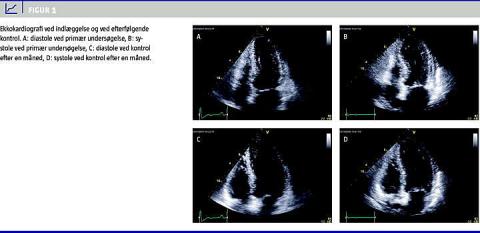

En 66-årig kvinde blev indlagt første juledag på mistanke om nyligt ST-elevationsmyokardieinfarkt (STEMI). Hun var disponeret til iskæmisk hjertelidelse ved rygning, let overvægt, statinbehandlet hyperkolesterolæmi og familiehistorie. Aftenen før indlæggelsen opstod der akut trykken i brystet i relation til stort familiært stress under julehøjtiden. Brystsmerterne bestod i ca. syv timer, hvorpå patienten følte sig træt og mat. Ved indlæggelsen ca. at halvt døgn efter smerteophør var patienten upåvirket og klinisk velkompenseret. EKG viste signifikant ST-elevation i prækordialafledningerne med efterfølgende udvikling af negative T-takker i disse afledninger. Blodprøverne viste, at CK-MB var faldende fra 27 mikrogram/l (normal < 5 mikrogram/l), og at troponin I var faldende fra 9,01 mikrogram/l (normal < 0,50 mikrogram/l). Ekkokardiografi ved indlæggelsen viste apikal ballonering og en estimeret uddrivningsfraktion (ejection fraction , EF) på 30% (Figur 1 ). Venstre ventrikel var ikke dilateret, og der var ingen signifikant klappatologi eller udløbsobstruktion. På baggrund af de kliniske fund og tidsforsinkelsen fra smertedebut fandtes der ikke indikation for akut KAG. Patienten blev behandlet med lavdosis-acetylsalicylsyre, clopidogrel, statinpræparat, betablokker og angiotensin converting enzyme (ACE)-hæmmer. I første indlæggelsesdøgn sås en enkelt asymptomatisk episode med nonsustained ventrikulær takykardi. Det kliniske forløb var derpå stabilt, og KAG på anden indlæggelsesdag viste lette diffuse forandringer uden angiografiske tegn til ustabile koronarplaques. Patienten blev udskrevet i velbefindende fire dage efter indlæggelsen under diagnosen AMI recens. Ved ambulant kontrol efter en måned var patienten i velbefindende, og ekkokardiografi viste fuldstændigt normaliserede forhold med normal EF (Figur 1). På baggrund af det samlede forløb blev diagnosen herefter revideret til TK.